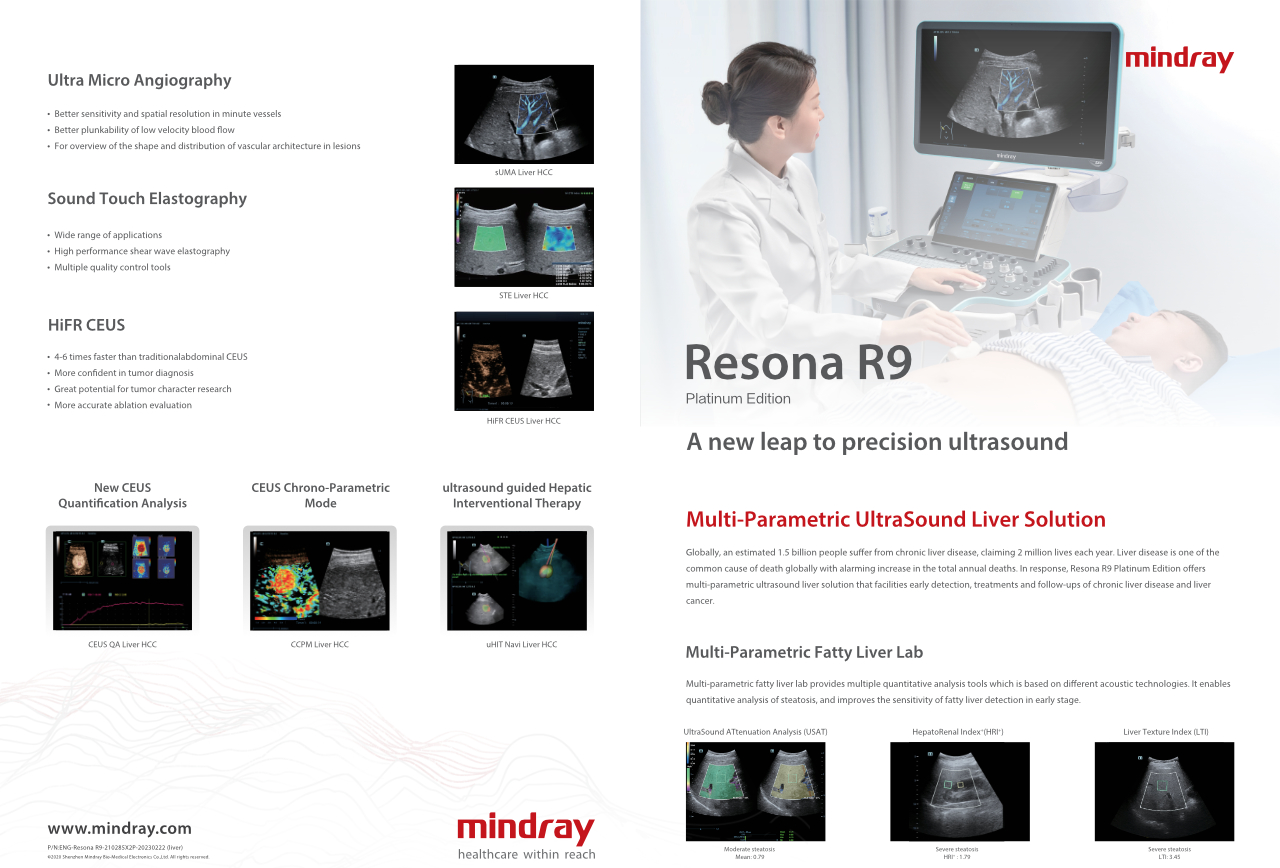

How Clearly Can You See a Liver?

Ultrasound contrast imaging plays a significant role in identifying focal liver lesions, such as hemangioma or liver cancer.

Ultra-wide non-linear UWN+ contrast imaging technology provides better penetration, higher contrast-tissue ratio, with lower MI and longer perfusion time observation.